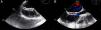

Figure 1.

TEE images demonstrate that the occluder device was properly deployed in the middle part of the interatrial septum (A) and there was no residual shunt through it (B).